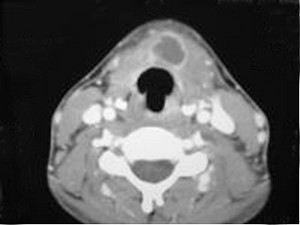

| 十产岁患者,女性,因颈前正中包块3年入院,查体:颈前胸锁乳突肌前缘上1/3外可触及一圆形包块,囊性,无压痛,不随吞咽上下活动。 |

6.CT检查结果见下图,本患者应考虑为 ( )![]() ![]() ![]() ![]() |

| 正确答案:6.C;7.E |